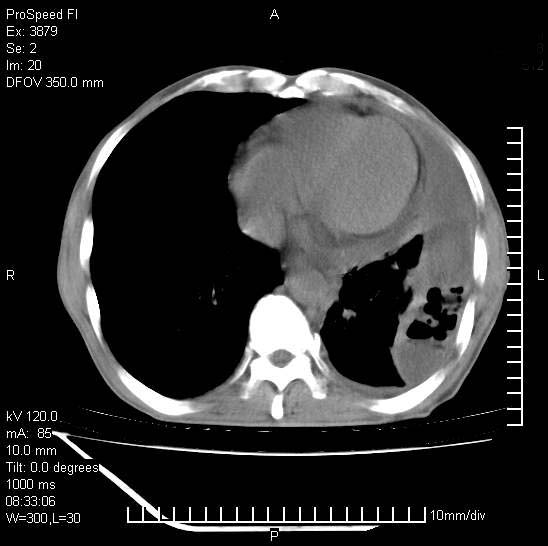

以下是引用37度在2008-6-6 11:20:00的发言:[br]1.包裹性积液,多考虑结核性;[br]2.穿刺术后改变。